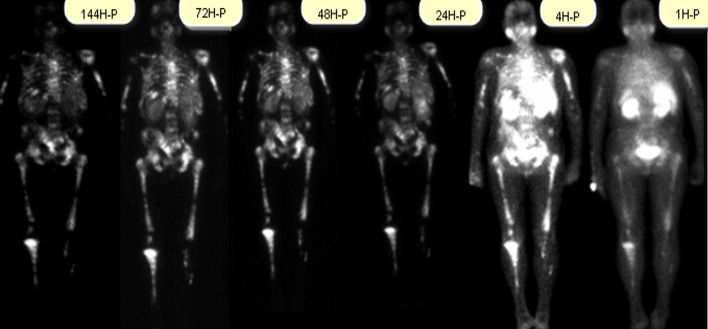

Material and methods: This study investigated absorbed doses to different organs in 9 mCRPC patients during their first treatment cycle. Whole-body planar images were acquired at 1 ± 0.5, 4 ± 0.5, 24 ± 2, 48 ± 2, 72 ± 2, and 144 ± 2 h post-injection, with SPECT/CT images obtained at 24 ± 2 h. Absorbed doses were calculated for five organs and the entire metastasis regions using GATE, OLINDA, and IDAC platforms. The spherical method was used to determine and compare the absorbed doses in metastatic regions and undefined organs in OLINDA and IDAC Phantom.